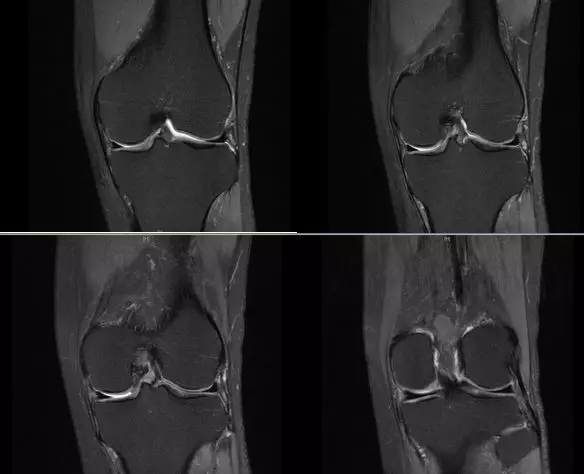

膝关节内侧副韧带

膝关节后外侧结构

内侧支持带撕裂

韧带结构:形态,张力,质地,连续性

半月板:完整性,形态,质地